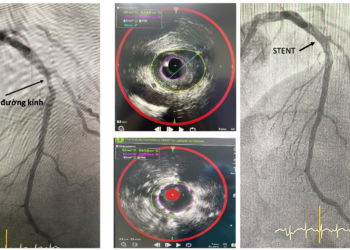

Ứng dụng NIRS–IVUS: Đột phá trong phát hiện sớm “mảng bám nguy hiểm” gây bệnh mạch vành

Kỹ thuật NIRS–IVUS: Tầm soát mảng xơ vữa mạch vành nguy hiểm Bệnh viện Đa khoa Khánh Hòa ứng dụng ...